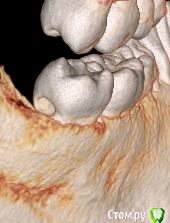

Александр23712 Опубликовано 3 октября, 2020 Поделиться Опубликовано 3 октября, 2020 (изменено) Всем здравствуйте! Я просматриваю частенько вопросы пациентов, ответы на них, недавно была тема вот с таким случаем (см. картинки). Тут вот я и задумался, мы это лечим как обычный второй класс, т.е. доступ с окклюзионной поверхности, сносим все, что выше, и восстанавливаем с помощью Супермата/Тоффльмайера/замковых матриц? При таких концевых дефектах получается и коффер не одеть? В теме был еще вариант про удаление-имплант, но это прям радикально мне кажется. Вот такое должно получиться решение?(картинка 3). Никак не могу смириться с тем, что в некоторых случаях надо иссечь своих тканей столько же, а то и больше, чем сам дефект Изменено 3 октября, 2020 пользователем Александр23712 Ссылка на комментарий